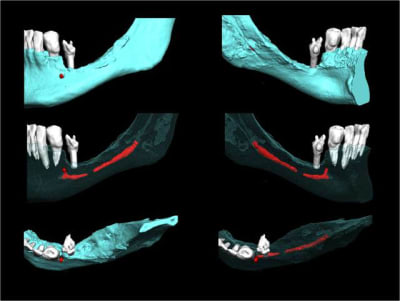

Il commence au trou mentonnier qui est situé à l'apex de la 6 ( rare) de la 5 ou de la 4, et il assure l'innervation du bloc IC. Il est conseillé de le respecter sur ses 4-6 premiers mm pour éviter une lésions nerveuse pouvant mal cicatriser et provoquer des décharges de neuro transmetteurs, d'où des douleurs cédant très difficilement aux antalgiques

Pour visualiser le trou mentonnier, il convient de décoller le périoste pour le mettre en évidence si tu as peur d'être trop proche. Le voir c'est l'éviter !

> Certains poseraient surement sans scan tellement c'est facile

si tu dis ça c'est qu'il doit y avoir une sacré baïonnette avec une hauteur osseuse disponible de 5-6 mm

Tu peux le voir comme cela ou tient si j’ai un cas similaire quel sont les solutions. ..distraction, greffe de pariétal, greffe allogène, PPA, rien…. Un praticien ma demandé de faire un guide pour une réhabilitons complète mandibulaire avec 2 implants position 36, 46 de 10mm. Ma réponse mais Docteur cela ne passe pas « si, ils seront bi-cortical » (l’apex de l’implant devait éffracter légèrement la zone ou passe l’artère linguale). Je ne pense pas que cette démarche soit courante, qu’elle se renouvellera fréquemment mais maintenant je sais qu’elle est réalisable.

c'est dingue ! L'artère linguale, le nerf lingual....brrrrrrr j'en ai froid dans le dos.....

Heureusement qu'avec un guide chir on évite tout ça...... et c'est à la porté de tout le monde..... si si